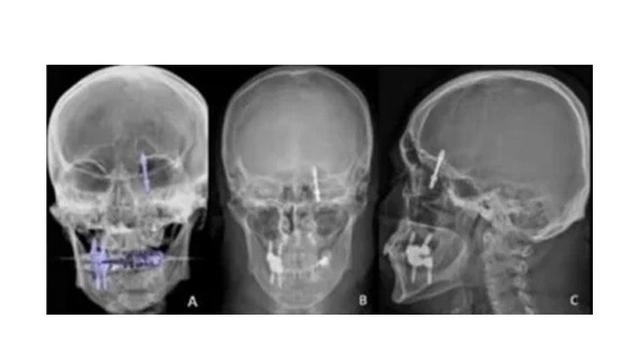

Sekrup logam yang menembus tulang rahangga hingga masuk ke rongga otak ini pun membuat Yilmaz menjerit kesakitan. Sang dokter gigi yang akhirnya menyadari situasi serius memilih melakukan rontgen. Diketahui jika sekrup tersebut terletak di rongga dekat otak hingga mengancam nyawa Yilmaz.

Dokter gigi tersebut langsung membawa Yilmaz ke UGD Rumah Sakit Universitas Uludag. Dirinya juga langsung dijadwalkan untuk menjalani operasi darurat.

Usai menjalani operasi, sang dokter berhasil melepas sekrup logam tanpa menyebabkan kerusakan otak. Dirinya juga harus menjalani pemulihan selama beberapa hari sebelum akhirny boleh dipulangkan.